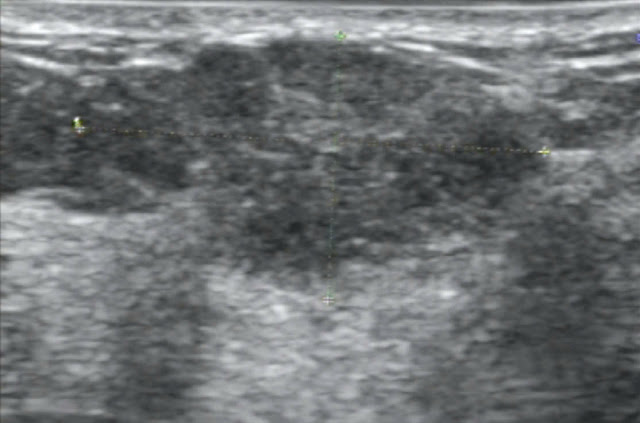

Trường hợp siêu âm tuyến vú 01:

- Bệnh nhân nữ, 49 tuổi

- Lý do siêu âm tuyến vú kiểm tra.

- Hình ảnh siêu âm: tổn thương echo kém, hình không đều, kt

# 25x18mm, trục song song mặt da, bờ có một phần không xác định, halo (+) vị

trí 3h ->9h, âm phía sau tổn thương không đều, xâm nhiễm da.

- Giải phẫu bệnh CARCINÔM CỦA VÚ, XÂM NHẬP, DẠNG NST, ĐỘ 2

(INVASIVE BREAST CARCINOMA OF NO SPECIAL TYPE, GRADE 2).

Nhuộm hóa mô miễn dịch tế bào u, có:

ER: (+) 100%; cường độ: 3; Allred score: 8/8

PR: (+) 100%; cường độ: 3; Allred score: 8/8

Her-2: (-)